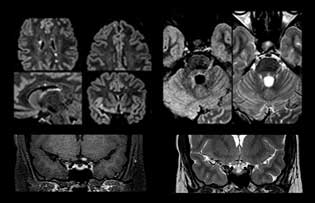

“For MS imaging in the spine, the basic examination includes a sagittal T2 and a post-contrast sagittal T1-weighted sequence in the whole spine. These are done in two stacks and using thin slices, for example 2 mm, without gap. As in the brain, the T2-weighted sequence visualizes the overall lesion load and helps determine if lesions are old or new. The post-contrast T1- weighted sequence helps in assessing if a lesion is new. We will sometimes add a T1 inversion recovery sequence, which has very good sensitivity, if we don’t find any lesions on T2,” Dr. Savatovsky says. “Additionally, if there is contrast enhancement outside the spine, it’s usually not MS but another kind of inflammation.”

Dr. Savatovsky uses five or six different ExamCards for imaging a mass or a known tumor in the brain. “If there is a mass in the brain we try to characterize it to inform the neurologist for determining next steps or to help neurosurgeon prepare for a surgery or biopsy. For follow-up after treatment we have different protocols for different treatments and we adapt for intra- or extra-axial tumors.” “That is the most comprehensive exam we would do. Ingenia has the good spatial resolution and high SNR to provide all this information, and the flexibility to use shorter sequences, so we can do a very comprehensive examination in a limited time.”

“The biggest challenges are properly characterizing the lesion and giving the surgeon all the information needed, such as the location of vessels and functional areas. Sometimes a very comprehensive exam is necessary, such as when a mass has been discovered at another hospital after which the patient is referred to us. We then do both lesion characterization and preoperative imaging in one exam, so both morphologic and functional assessment. For morphologic assessment we will use pre- and post-contrast T1-weighted imaging, FLAIR to assess infiltration, and diffusion. For functional characterization we will perform perfusion, spectroscopy, and susceptibility weighted imaging to look for micro vessels or micro hemorrhage inside the lesion[4]. For preoperative imaging we perform specific morphologic imaging that is compatible with the navigation system; depending on the location of the tumor, we would do fMRI or DTI.”